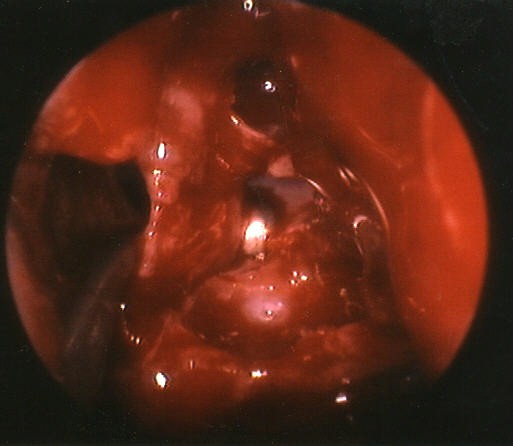

The picture above demonstrates an interesting finding. It looks as though the patient has two middle turbinates on her left side. Actually the more lateral "middle turbinate" is an air cell connected fully with the agger nasi cell above. It seemed to be an inferior extension of the agger nasi, or a concha bullosa that "pinched off" to form a psudo-turbinate. The uncinate process remained in place lateral to the turbinate, so it was not a pneumatization of the uncinate. |